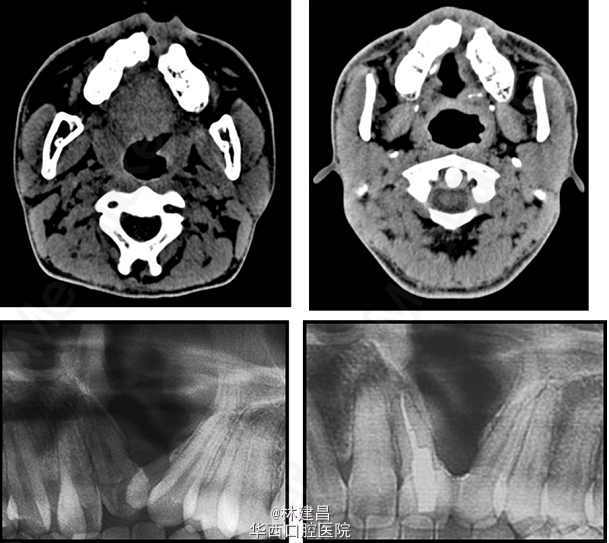

患者为18岁男性,面形凹,上颌骨发育不足,有一处重度牙槽突裂,因面部不美观,来正畸科求治。综合评价其病情后,为患者提供了手术和非手术两种方案,患者最终决定了非手术方案。此后患者的正畸治疗包括了扩弓、拔牙和牙周修复会诊。正畸治疗使用了新亚MBT托槽0.022x0.028(国产托槽也有好货!)配合微种植钉,排齐整平恢复I类磨牙关系。治疗完成1年后复诊。